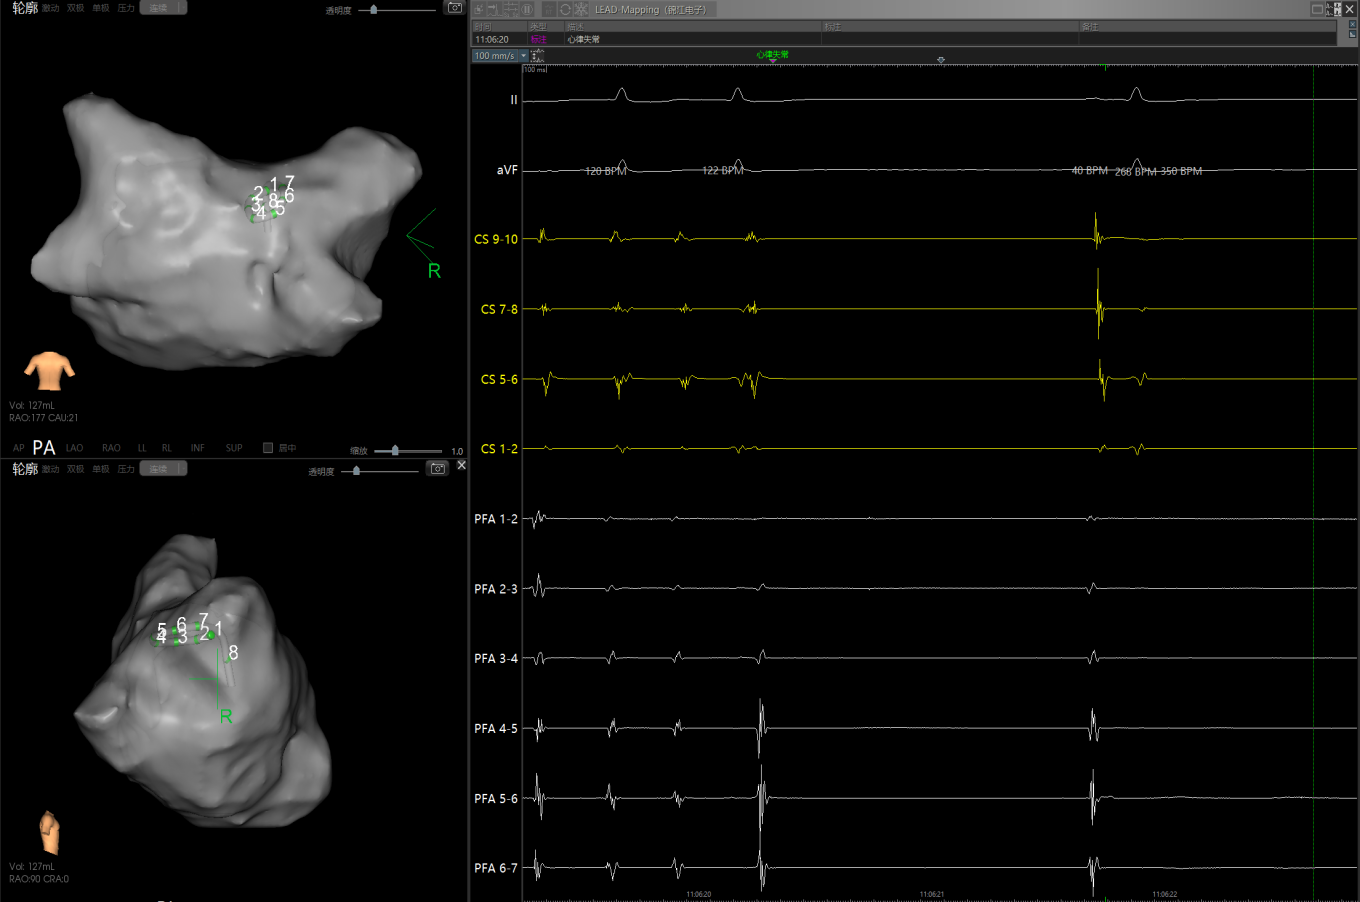

图1 患者因心功能差行电复律,窦律无法维持